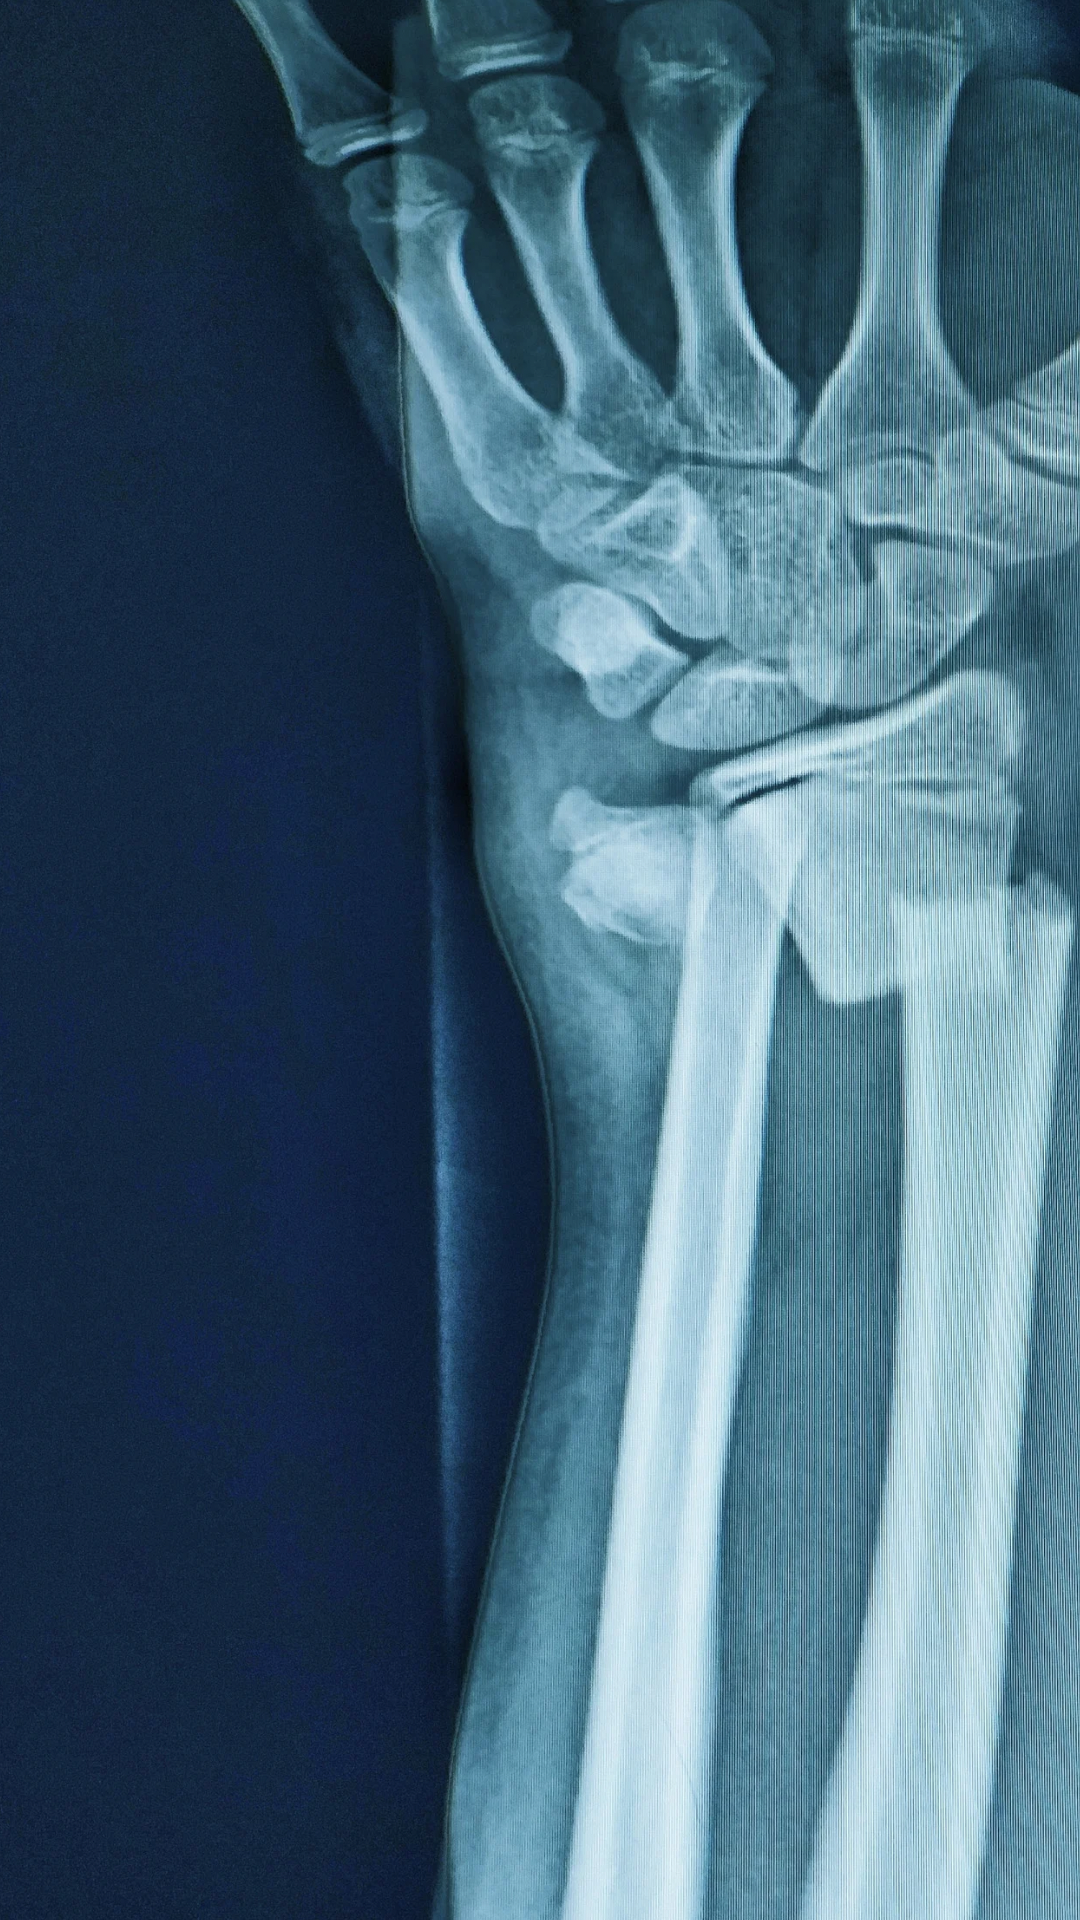

Surgical treatments of fractures range from closed or open reduction of the fracture (fragments alignment) and fixation with implants. Fixation can be internal or external.

For a successful recovery, the diagnosis is basic. At CIFO our patients are thoroughly evaluated, using clinical tools and making use of the most advanced diagnostic technology.